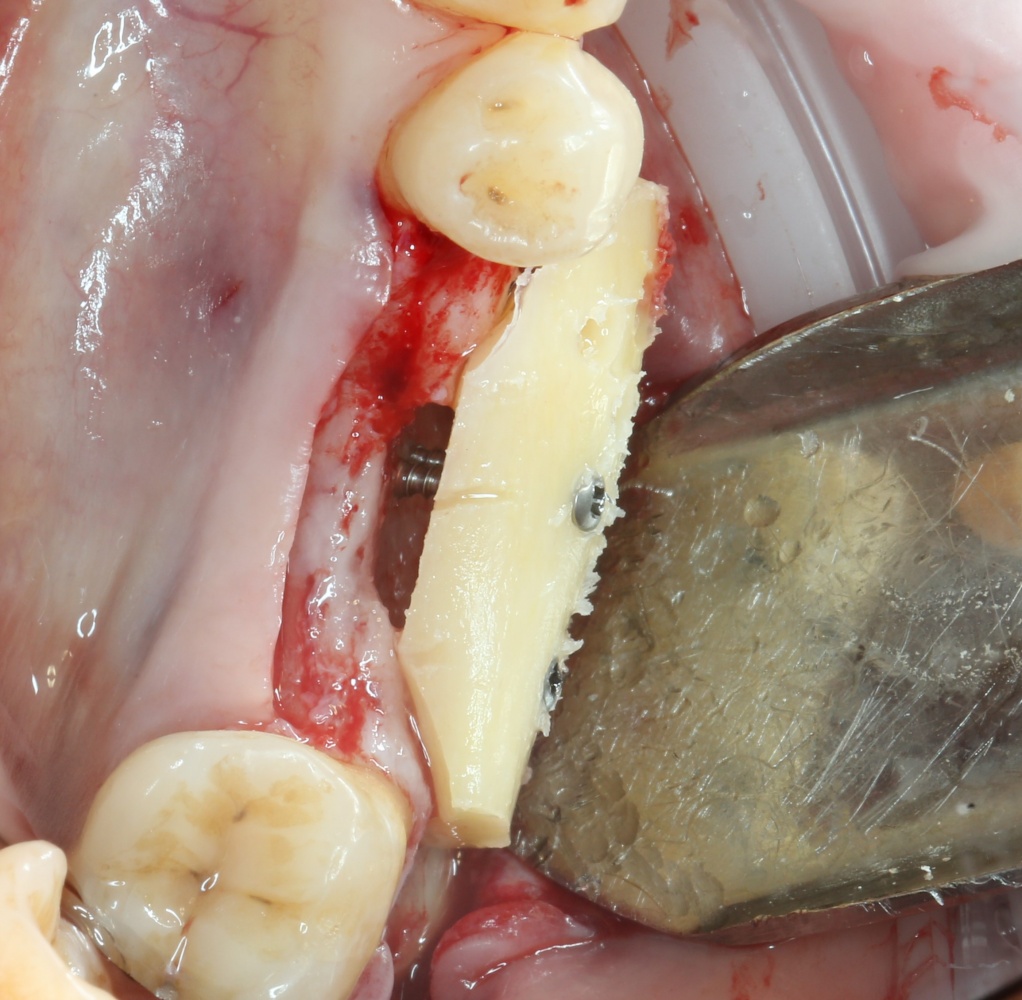

Следующим этапом происходит формирование и забор аутокостного фрагмента для пересадки:

A09A5447 (2) A09A5448 (2)

Далее, примеряем и адаптируем костный блок:

A09A5449 (2) A09A5450 (2)

Готовим его к фиксации:

A09A5451 (2)

Многие ошибочно предполагают, что большое количество дырок в блоке нужно для того, чтобы «всё лучше срослось». На деле, большое количество отверстий в аутокостном фрагменте даст нам возможность переставлять вины и адаптировать его «на месте». А это особенно важно для одномоментной установки имплантов, потому что винты не должны попасть в проекцию будущей лунки.

Фиксация костного блока:

A09A5452 (2) A09A5453 (2)

Для этого стоит использовать длинные винты. В противном случае, при подготовке лунки под имплантат костный блок может отлететь.